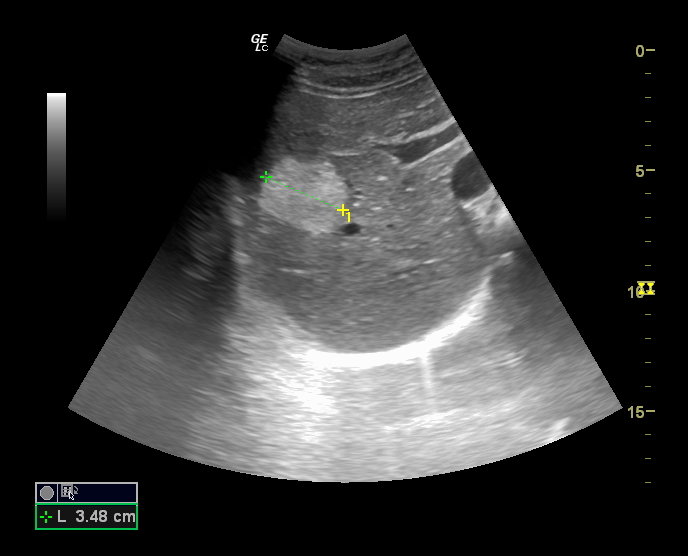

Hallazgos ecográficos

En la última ecografía realizada en febrero de 2023 presenta múltiples hemangiomas (lesiones hiperecogénicas), el de mayor tamaño en lóbulo caudado de 41 x 38 mm, segmento VIII dos, uno de 53 x 40 mm y otro de 17 mm, en segmento IV de 16 mm y en segmento VII de 9 mm.